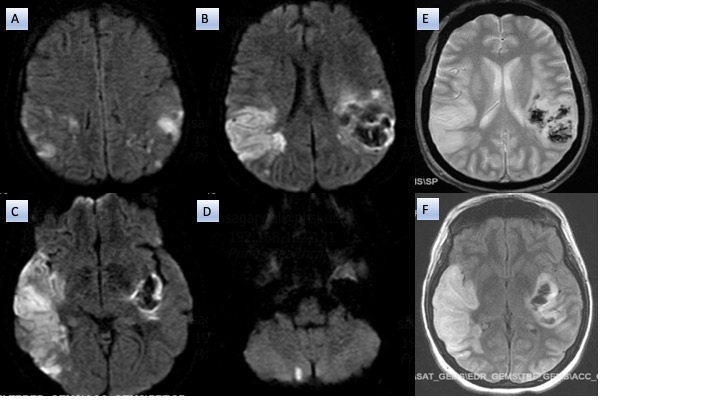

A 36-year-old woman, with drug use disorder was found unconscious with fentanyl and needles nearby. On initial evaluation, she met criteria for systemic inflammatory response syndrome: fever (T 101°F), tachycardia (HR 142 bpm), and hypotension (BP 70/43 mmHg). She was unresponsive to noxious stimuli and had a 15 cm chronic soft tissue ulcer on her right leg. Immediate management was started including endotracheal intubation, mechanical ventilation, followed by intravenous fluid resuscitation, vasopressors, and empiric Meropenem due to documented beta-lactam anaphylaxis. Laboratory studies were remarkable for elevated white blood cell count (36,700/μL), procalcitonin (17 ng/mL), CRP (13 mg/dL), ESR (110 mm/h), and lactate (7 mmol/L). Acute ischemic infarcts in bilateral frontoparietal regions and a punctate infarct in the right cerebellum were demonstrated on computerized tomography. Transthoracic and transesophageal echocardiography identified a 23 mm mobile vegetation on the aortic valve with severe regurgitation. Serratia marcescens, a gram negative fermenter bacilli susceptible to Meropenem, grew on blood and wound cultures. On hospital day 3, severe neurological deficit was observed due to hemorrhagic transformación of the left middle cerebral artery territory infarct.

This case underscores the complexity of infective endocarditis in the context of drug use disorders. In this case, a chronic wound represented an unconventional but lethal portal for gram-negative seeding of the aortic valve. Infective endocarditis goes beyond infection and requires a multidisciplinary approach with shared decision making. Though the presence of a large, mobile vegetation, severe valve dysfunction, and systemic embolization were indicative of urgent valve replacement; the hemorrhagic transformation of the MCA territory infarct precluded safe anticoagulation delaying aortic valve replacement. In addition, persistent severe neurological deficit required long-term supportive care such as tracheostomy and percutaneous endoscopic gastrostomy. Early recognition of drug use disorders, multidisciplinary collaboration, and integration of resources are essential to improving outcomes in this high-risk population.